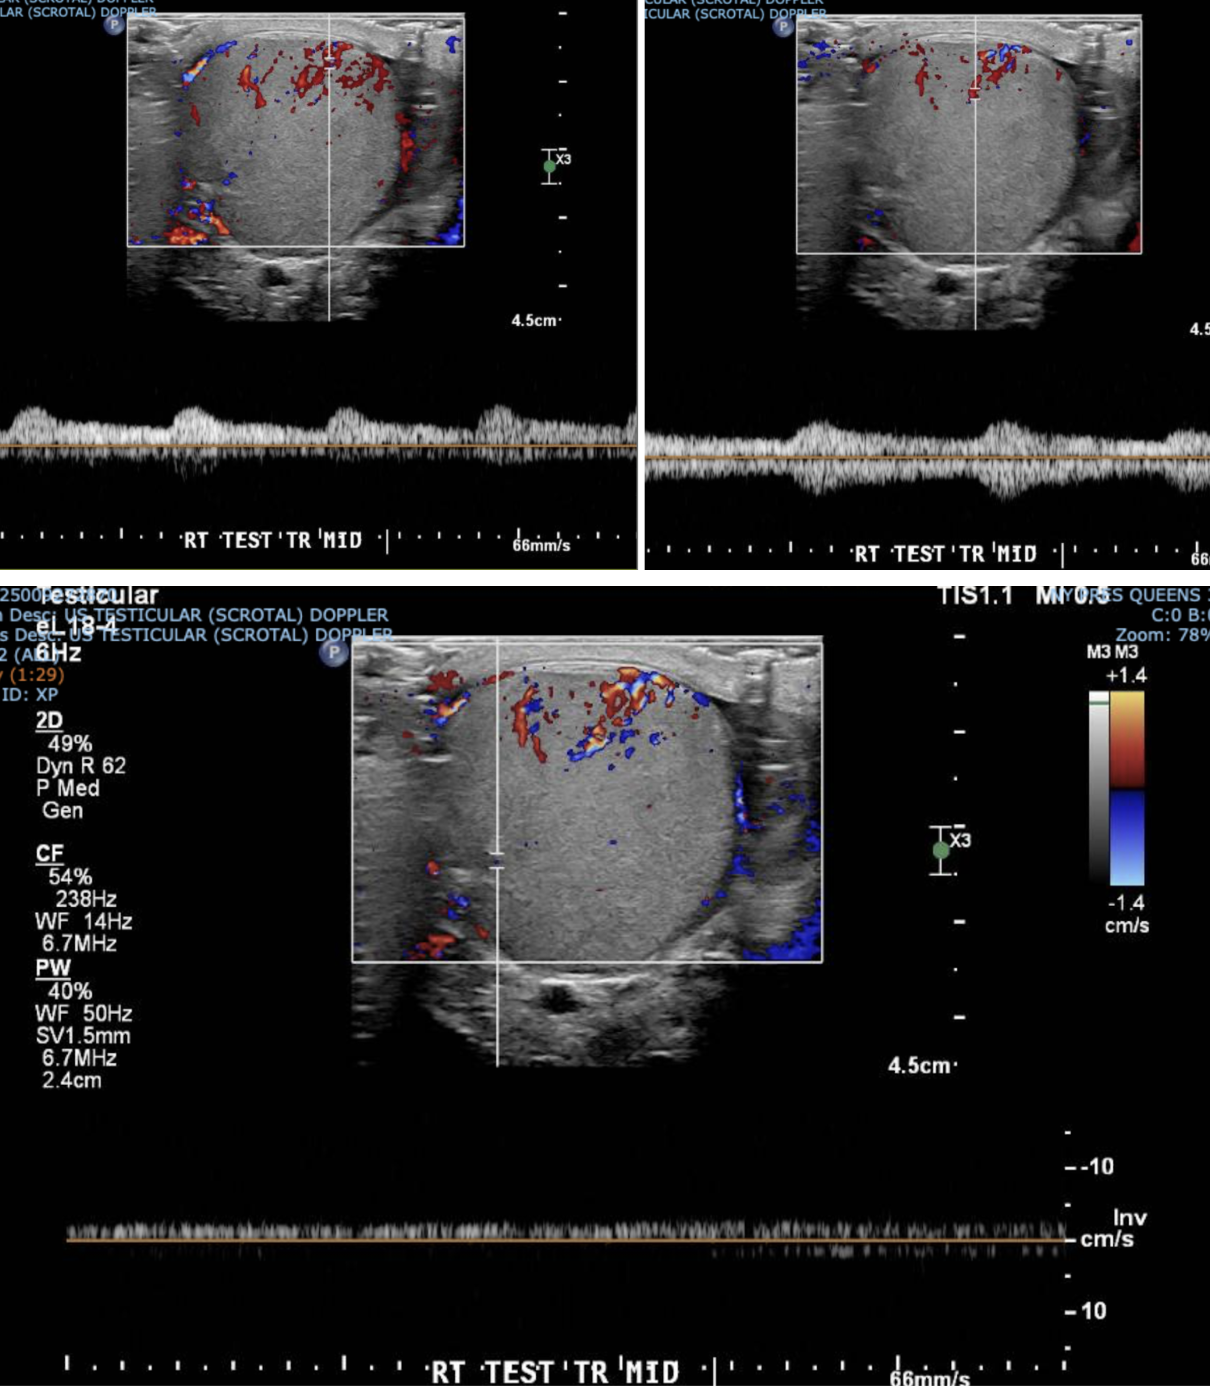

We made sure to confirm blood flow to BL testicles. Just because a patient has testicular rupture does not mean they do not have testicular torsion as well!

I want to reiterate that color doppler is imperative for determining vascular integrity, which will ultimately assist in providing the correct disposition for the patient.

Absent Flow: Indicates ischemia or infarction, requiring immediate surgical salvage.

Decreased Flow: Compare with the contralateral healthy testis. Asymmetric flow suggests injury.

Hyperemia: Occasionally seen in surrounding tissues due to inflammation.